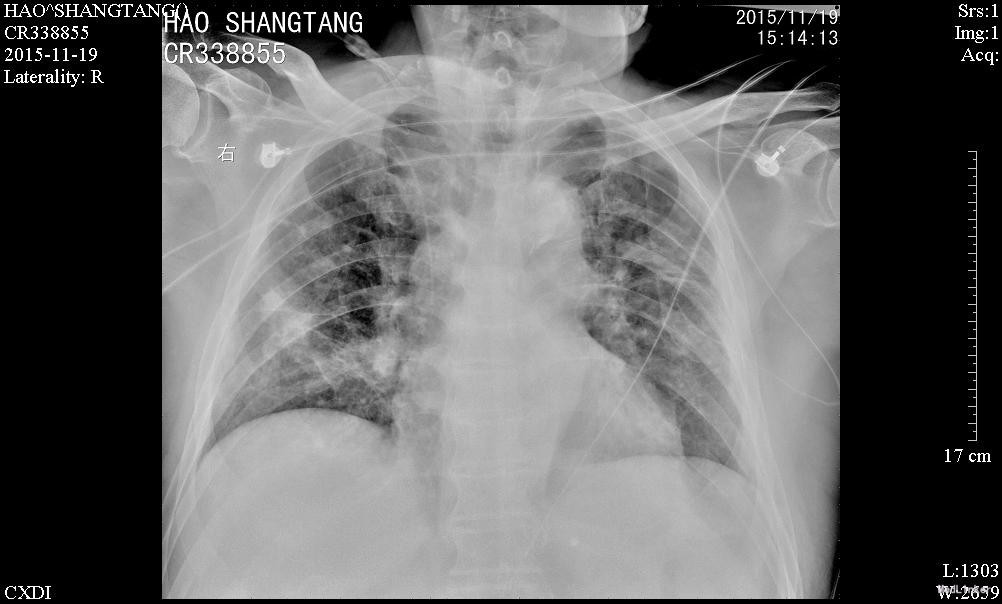

男,82岁,已婚,因“肢体抽搐伴意识障碍1天“入我院神经内科,因肺部感染加重10天后转入呼吸内科

入神经内科经舒普深抗感染及抗癫痫等治疗,无明显癫痫,但肺部感染加重,查见广泛耐药鲍曼不动杆菌及铜绿假单胞菌感染,转入呼吸科后给予美平联合舒普深治疗,1周后成功拔管脱机,2周后体温完全正常,转入康复科继续治疗